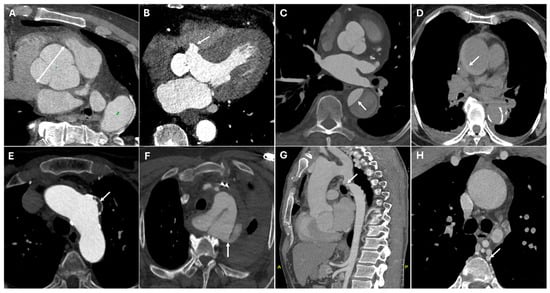

| Bentall Procedure | Aortic root aneurysms, Type A dissection | Composite graft with valve, coronary reimplantation | Tubular graft replacing aortic root, prosthetic valve |

| Cabrol Procedure | Complex reoperations, severe atherosclerosis | Prosthetic conduit for coronary artery reimplantation | Graft with parallel interposed conduit |

| Yacoub Procedure | Aortic root aneurysms, valve-sparing repair | Synthetic graft remodeling sinuses of Valsalva | Scalloped aortic root graft with preserved valve |

| David Procedure | Marfan syndrome, younger patients | Valve-sparing root replacement with graft | Native valve reimplanted into supportive graft |

| Hemiarch Repair | Limited aortic arch pathology | Zone 0 reconstruction with lesser curvature graft | Graft in the aortic hemiarch |

| Hybrid Type I Repair | Extensive arch disease | Arch debranching, stent landing in zone 0 | Endovascular stent plus revascularized arch vessels |

| Hybrid Type II Repair | Extensive arch disease | Arch debranching, open surgery and stent landing in zone 0 | Tubular surgical graft with high-density metallic stent |

| Hybrid Type III Repair | Extensive arch disease | Open graft extending to descending aorta, endovascular stent | Tubular surgical graft with high-density metallic stent |

| Elephant Trunk Technique | Staged repair of extensive aortic disease | Open arch graft extending into descending aorta | Floating tubular graft within descending aorta |

| Frozen Elephant Trunk | Single-stage aortic arch + descending repair | Endovascular stent incorporated within open graft | Seamless transition between proximal graft and distal stent |

| Reverse Elephant Trunk | Staged descending arch repair | TEVAR followed by open arch surgery | Combination of open and endovascular grafts |

| Buffalo Trunk Technique | Combined arch and descending aorta repair | Open arch graft with endovascular stent | Hybrid repair with visible proximal graft and extended stent |

| TEVAR | Descending aortic aneurysms, dissections | Endovascular stent placement | High-density metallic structure conforming to aortic lumen |